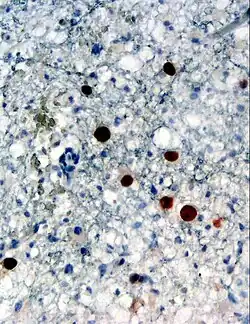

Das JC-Virus gelangt bei T-Zell-Immungeschwächten wahrscheinlich vom Ort seiner Persistenz (möglicherweise Nierengewebe und/oder Knochenmark) über Leukozyten in das zentrale Nervensystem und repliziert in der weißen Substanz im Großhirn, im Hirnstamm, im Kleinhirn (Zerebellum) und im Rückenmark. Es handelt sich um eine Entmarkungskrankheit (Demyelinisierungskrankheit), das heißt, die Nervenscheiden (Myelinscheiden) der Oligodendrozyten, welche die Nervenfortsätze (Axone) der Neurone umhüllen, werden befallen und degenerieren. Da die graue Substanz hauptsächlich aus Nervenzellkörpern besteht und nur zu einem geringen Anteil aus Axonen, ist sie von der Infektion fast nicht betroffen. Histologisch handelt es sich um eine entzündliche Entmarkung mit perivaskulärer Leukozyteninfiltration. Insbesondere die ausgeprägte Polymorphie der infizierten Gliazellen ist typisch. Die neuropathologische Diagnose wird durch den Nachweis von JC-Virus-Protein in der Immunhistochemie oder den Nachweis von JC-Virus-Genom in der In-situ-Hybridisierung bestätigt.